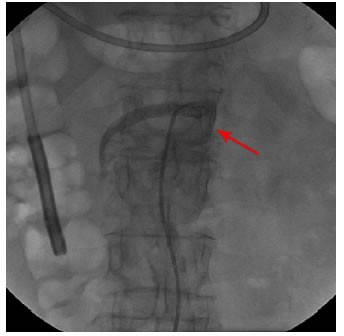

Por el riesgo de trombosis mesentérica e isquemia intestinal grave, la paciente se sometió a una angioplastia periférica de la arteria mesentérica superior con colocación de una endoprótesis (stent), procedimiento se que llevó a cabo sin complicaciones (figura 3).

La evolución fue satisfactoria; al día siguiente no presentaba dolor posprandial, náuseas ni vómito, y se había resuelto la sitofobia. En conjunto con el Servicio de Hemodinamia, se decidió darla de alta con tratamiento antiplaquetario dual y sin dabigatrán, por el alto riesgo de sangrado; tenía total tolerancia a la vía oral.